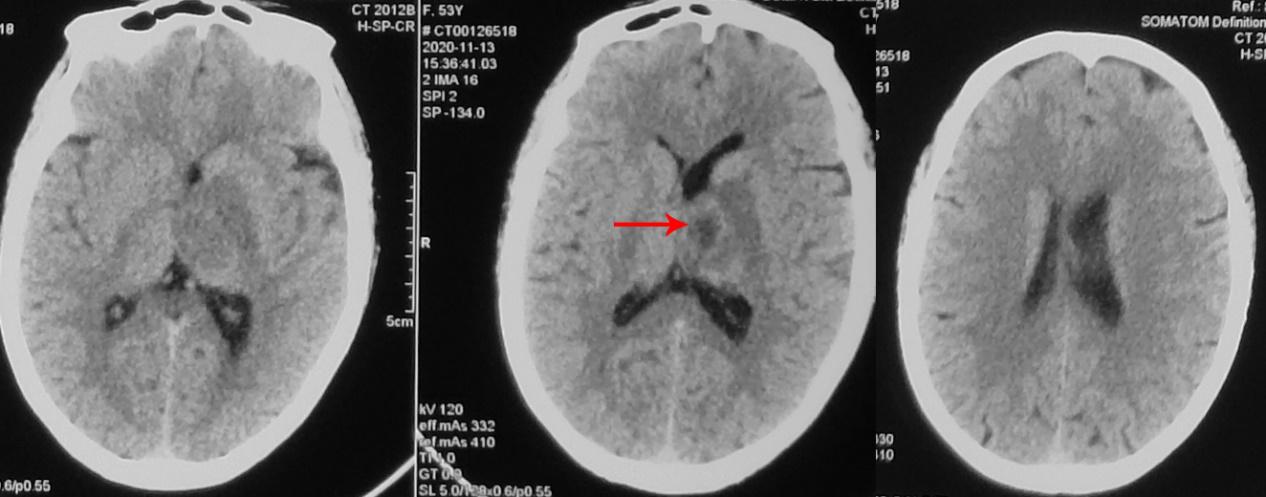

患者于2020年11月8日无明显诱因出现间断头痛。发病5天后,即2020年11月13日到当地的河南省潢川县某医院行头颅CT检查( 图-1 )发现左侧丘脑病变。

图-1: 2020年11月13日头CT